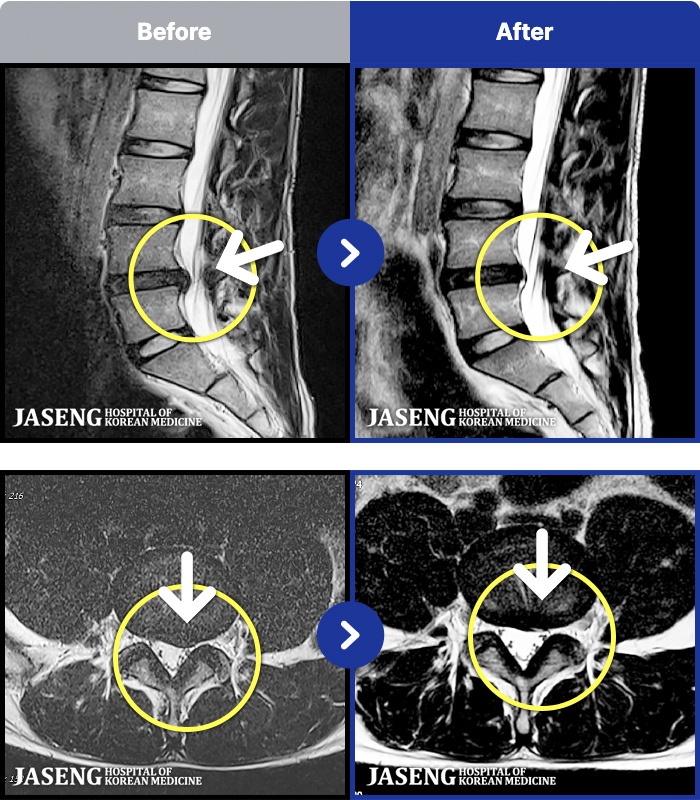

MRI ũ ʸ Ȯϼ.

[뱸] 19.11.28~25.05.06